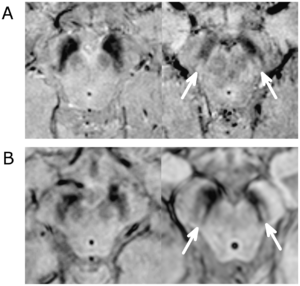

- 4.31 The Swallow Tail Appearance of the Healthy Nigrosome – A New Accurate Test of Parkinson’s Disease: A Case- Control and Retrospective Cross-Sectional MRI Study at 3T

- 4.32 Clinical and Computed Tomographic Predictors of Chronic Bronchitis in COPD: A Cross Sectional Analysis of the COPDGene Study